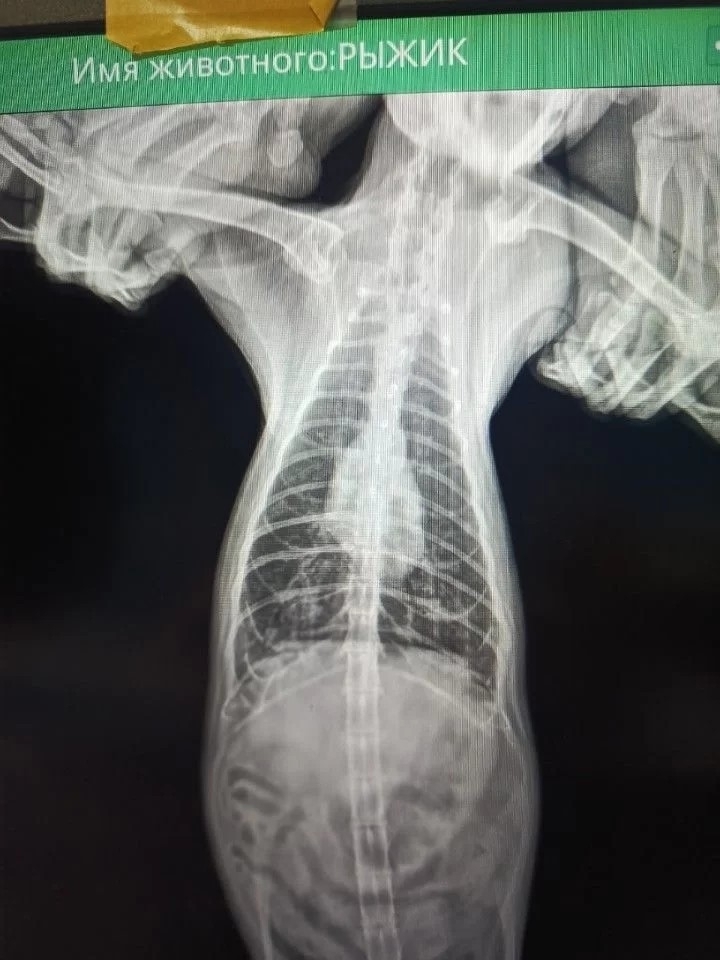

Но к концу 2023 года у Рыжика первый раз появились проблемы с дыханием. Возили в Воронеж, на время состояние стало лучше. Но в этом году одышка снова появилась и уже намного сильнее, лечение результата не дало. Иногда он задыхается ночью, вся семья не спит, но сделать ничего не может 😭😭😭

Объехали елецкие клиники, консультировались с врачами из других городов и все сходятся во мнении: надо делать бронхоальвеолярный лаваж (БАЛ) - процедуру под общим наркозом, которая как облегчит его состояние, так и поможет установить причину заболевания.